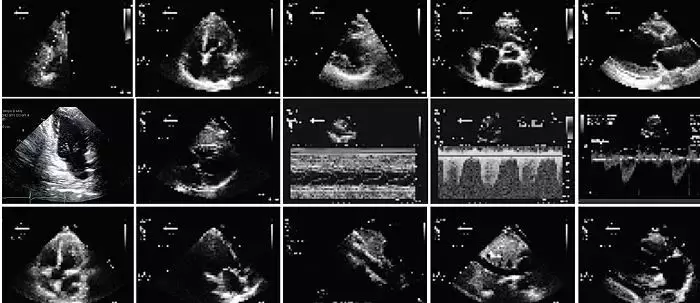

医药工业领域是人工智能系统应用的理想之地。医学检验、医生的面谈和过程被成文为患者病历,存为电子格式。AI系统可以摘要这些数据,从而决定较好和性价比较高的治疗方案。现在许多研究都在建造这种系统,许多文章描述关于分析纪录、扫描图像、产生患者健康的诊断和预言。譬如下图所示一个低分辨率的反映心脏跳动的心动图,用AI程序分离,取出最相关的部分,然后用解剖学的理解去进行诊断。

旧金山加州大学助理教授、心脏病专家Rima Arnaout训练一个神经网络去分类超声波心电图,在分辨微小而低分辨率图像方面比心脏病专家精确多了。下一步将用该图像信息去识别解剖结构和诊断心脏疾病和缺陷。

但是,Arnaout说:“我不会去做自己无法信服的诊断。”她用两个技术去搞懂她的分类器是怎么做出决定的。在封闭试验中,他考察测试图像的部分变化如何改变AI的回答;用显著图,她跟踪神经网络的最后回答返回到原图,去发现什么像素权重最高。这两技术说明图像的那些部分对AI做出结论最重要,正和专家看重的结构相重合。